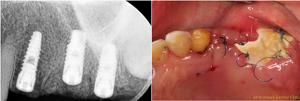

단점

- 치조골(잇몸뼈) 상태 파악의 한계

- 무절개 임플란트는 잇몸을 절개하지 않기 때문에, 치조골 상태를 직접 육안으로 확인할 수 없습니다.뼈의 결손, 경사, 두께 등이 충분히 파악되지 않아 예기치 못한 문제가 발생할 수 있습니다.

- 연조직(잇몸) 환경 개선 기회 상실

- 절개 방식과 달리 잇몸의 두께나 모양, 건강상태를 시술 중에 조정하거나 개선할 수 있는 기회가 적습니다.